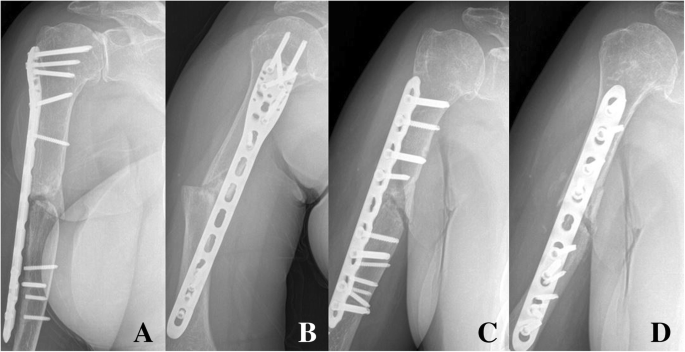

Медицинские снимки: Пластина в левом предплечье

Раздел: Альбом идей